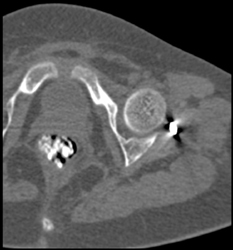

Hip Joint Effusion